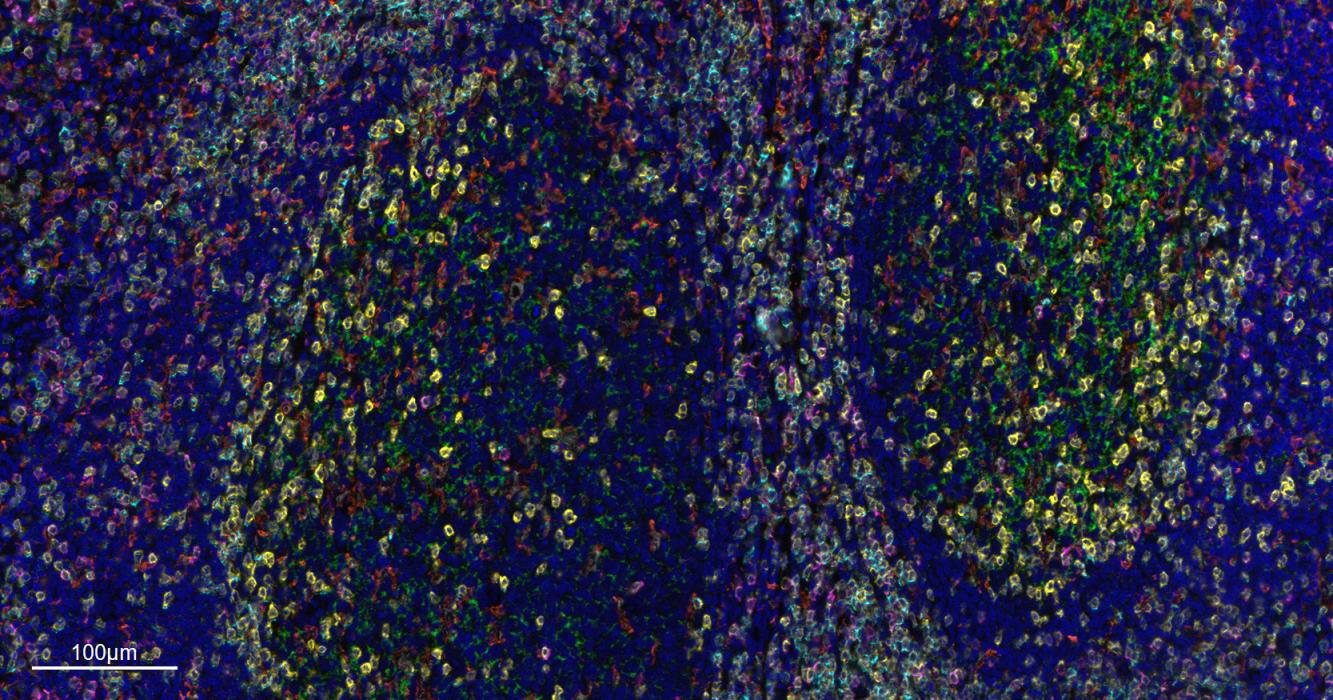

Paraformaldehyde-fixed, paraffin embedded Human Tonsil. Merged staining of anti-CD8A (bsm-34251M; 1:200; pink) anti-CD4 (bsm-52469R; 1:200; light blue) anti-CD3E (bsm-60002R; 1:200; green) anti-CD68 (bsm-60634R; 1:200; white) anti-CD11c (bsm-61135R; 1:200; orange) and anti-CD20 (bsm-63327R; 1:200; yellow) DAPI (dark blue) was used as a nuclear counter stain.